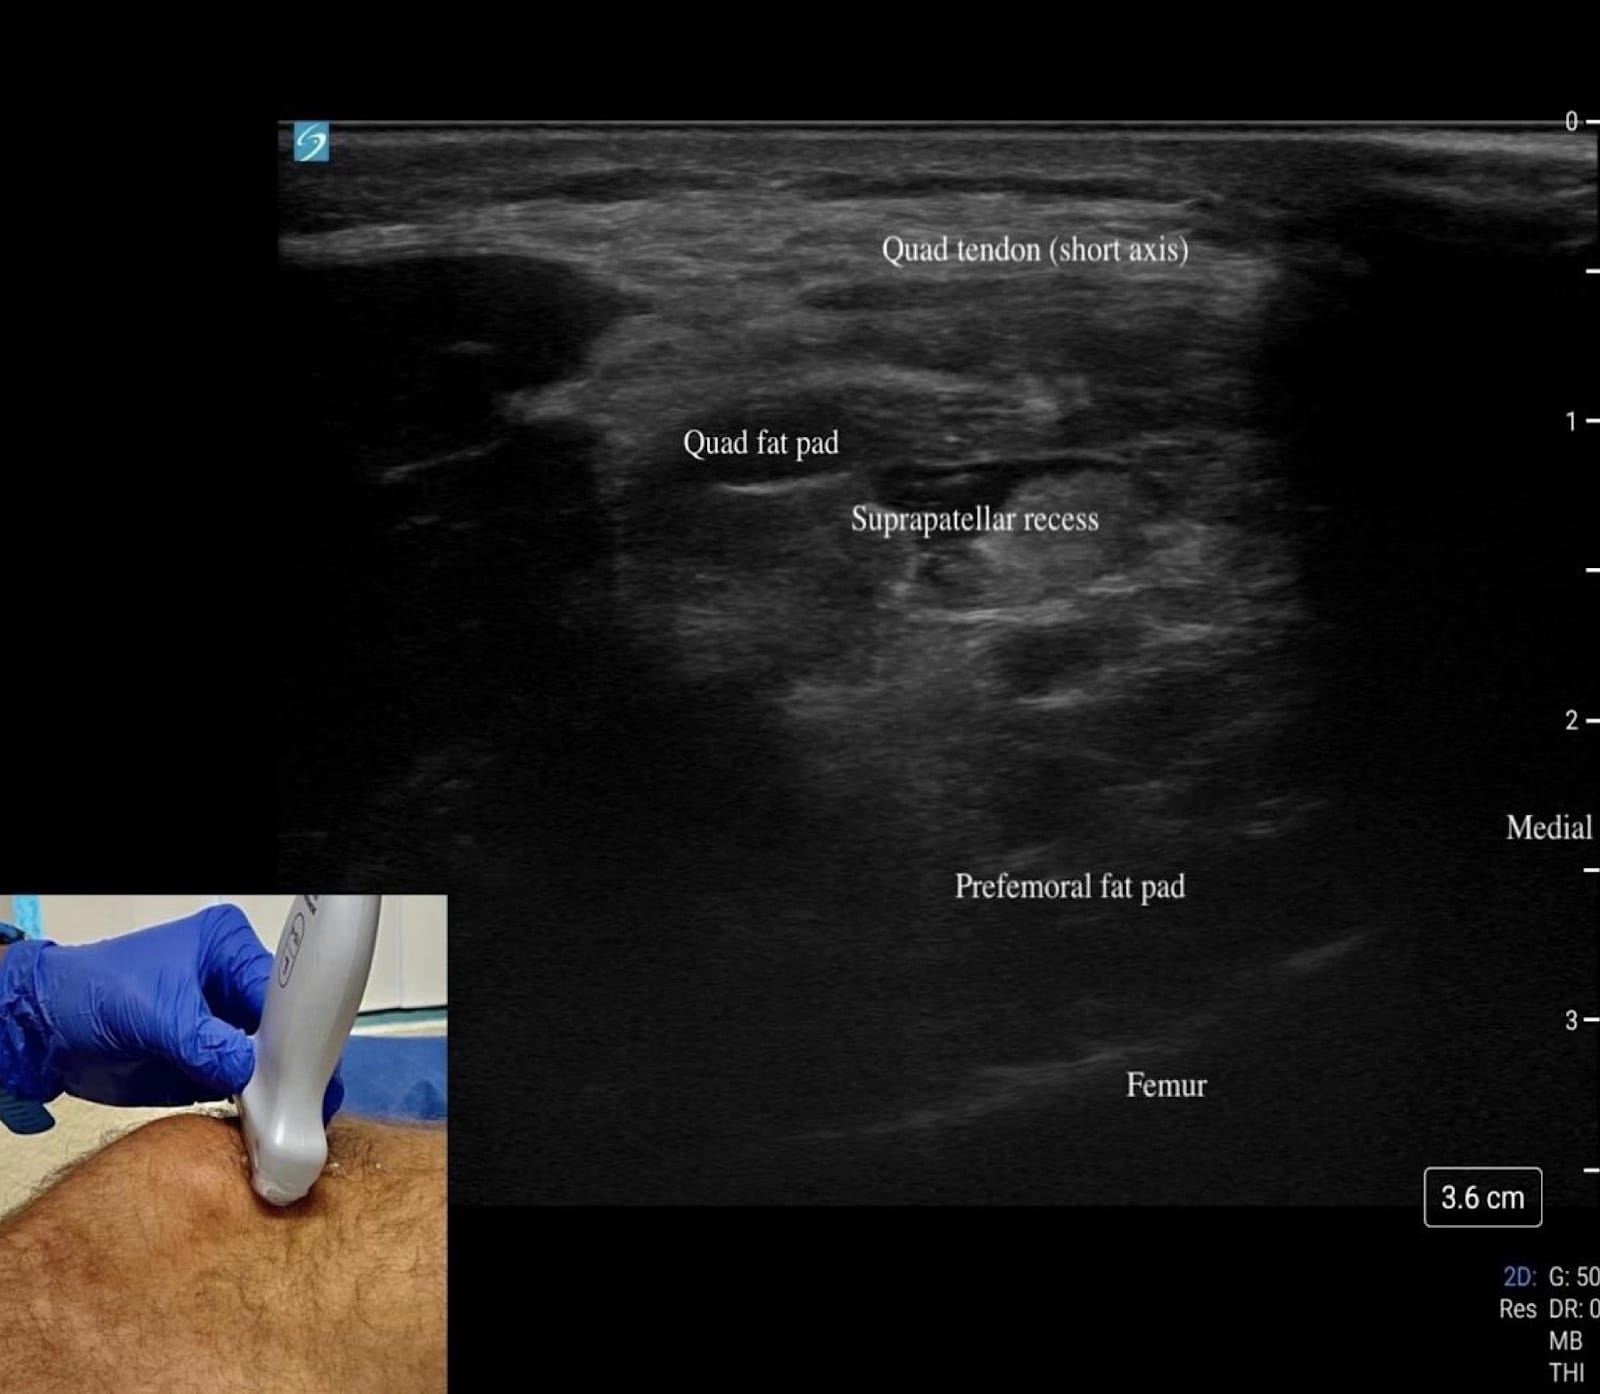

We recommend a high-frequency linear transducer (12–18 MHz). Providers can switch to a lower frequency transducer for larger body habitus or deeper structures. For anterior/medial and lateral visualization, the patient should be supine with the knee slightly flexed at 20–30° on a towel roll (Figures 1A and B, 2, and 3). For posterior, the prone position is preferred (Figure 4).

Begin by placing the transducer in short axis over the quadriceps muscle (“home base”). Rotate into long axis and scan distally over the tendon to the superior pole of the patella (Figures 1A and B).

Just beneath the tendon lies the quadriceps fat pad, followed by the suprapatellar recess, which appears as an anechoic stripe when effusion is present (Figures 5C, D).

The prefemoral fat pad above the femur provides another landmark. Continue to the patella itself in both long and short axis, assessing for cortical irregularities, fracture, or bipartite variants. Between the skin and bone lies the prepatellar bursa, a potential space for fluid that is best evaluated with minimal transducer pressure, and plenty of gel (Figure 5B).

Key Structures: Quadriceps tendon, patella, patellar tendon, suprapatellar recess (Figures 5A-D).